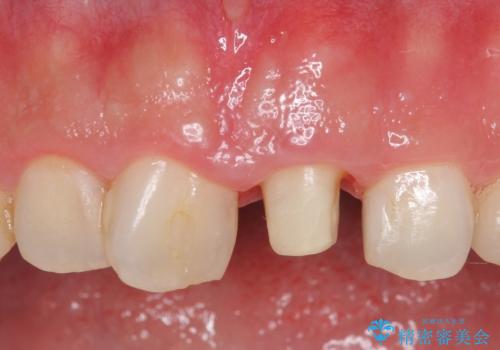

オールセラミッククラウン 長さが気になる前歯の改善

- 前歯の長さが気になるのでセラミックで治療したいといらっしゃった方の症例です。

御希望された再根管治療終了後、オールセラミッククラウンによる補綴を行いました。